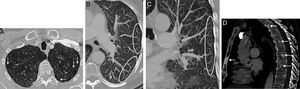

(A) Axial image of chest CT (pulmonary parenchymal window) showing linear thickening of the subpleural lung interstitium (arrows). (B) Maximum intensity projection (MIP) axial reconstruction (pulmonary parenchymal window) of left lung, showing a peripheral “tree-in-bud” pattern consisting of linear opacities forming predominantly subpleural branches (circled). See also the presence of small centrilobular nodules (arrow). (C) MIP coronal reconstruction (pulmonary parenchymal window) of the left lung, also showing the “tree-in-bud” pattern (circled). (D) Chest CT sagittal image (bone window) revealing multiple focal bone lesions (arrows) in the sternum and several vertebrae, consistent with bone metastases.

We report the case of a 58-year-old man, former smoker (20 pack-years), who presented with a 2-week history of progressive dyspnea and dry cough. Significant clinical history included prostate adenocarcinoma (Gleason score 6), treated with radiation therapy with curative intent 6 years previously, with no biochemical evidence of tumor relapse. Clinical examination revealed tachypnea and fine crackles on auscultation. Basal oxygen saturation was 88% and laboratory test findings did not suggest infection, although D-dimer levels were elevated. A chest radiograph showed bilateral diffuse interstitial involvement and prominent lung hila. Chest CT angiogram ruled out embolism on the main pulmonary, lobar or segmentary arteries, although multiple mediastinal and hilar lymphadenopathies were detected, along with severe interstitial involvement consistent with thickening of the subpleural pulmonary interstitium (Fig. 1A) and the presence of numerous centrilobular nodules and “tree-in-bud” images (Fig. 1B and C). Multiple focal bone lesions, predominantly sclerotic, were also observed in the vertebrae and sternum, consistent with metastasis (Fig. 1D). Given these radiological findings, PTTM secondary to prostate adenocarcinoma was suggested as an initial diagnosis, although other possibilities such as sarcoidosis or infection with an unusual pathogen were not ruled out. Four days after admission, the patient developed rapidly progressing respiratory failure that required urgent intubation. A few hours later, he suffered an episode of cardiorespiratory arrest with asystole and died despite prolonged attempts at cardiopulmonary resuscitation. The diagnosis of PTTM was confirmed on autopsy, which revealed an unsuspected undifferentiated occult gastric “signet ring” adenocarcinoma, with extensive metastases and multiple tumor embolisms in the small-caliber peripheral pulmonary arteries.